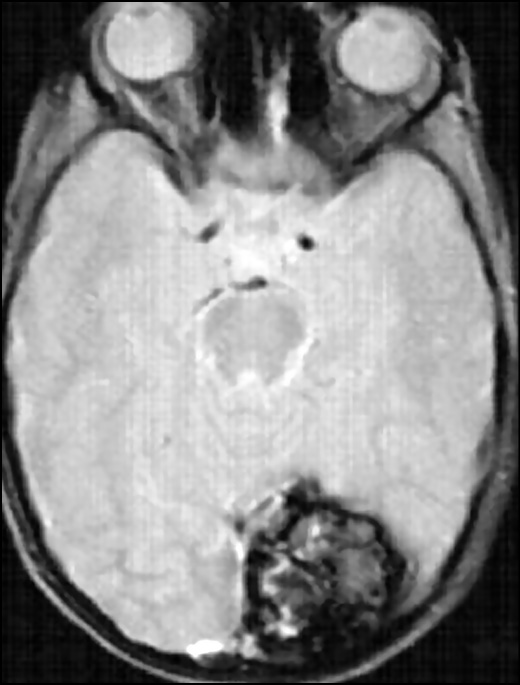

The combination of a reduced signal rim with a reticular nucleus of mixed hyper- and hypointensity on T2–WI with a high probability is a diagnostic sign of CM. For smaller CM lesions, a point area of hypointensity is assessed on T2–WI. Vasogenic edema accompanies lesions in perifocal regions, which are indicated by an increased signal intensity on T2–WI, and the mass effect usually does not appear even with a sufficiently large lesion if no relatively recent bleeding has occurred (Fig. 3) [17, 22].

Fig. 3. T2*GRE image in the axial view shows a large cavernous angioma in the left occipital lobe. Despite the significant size of the lesion, no perifocal edema and mass effect on the surrounding structures are found.